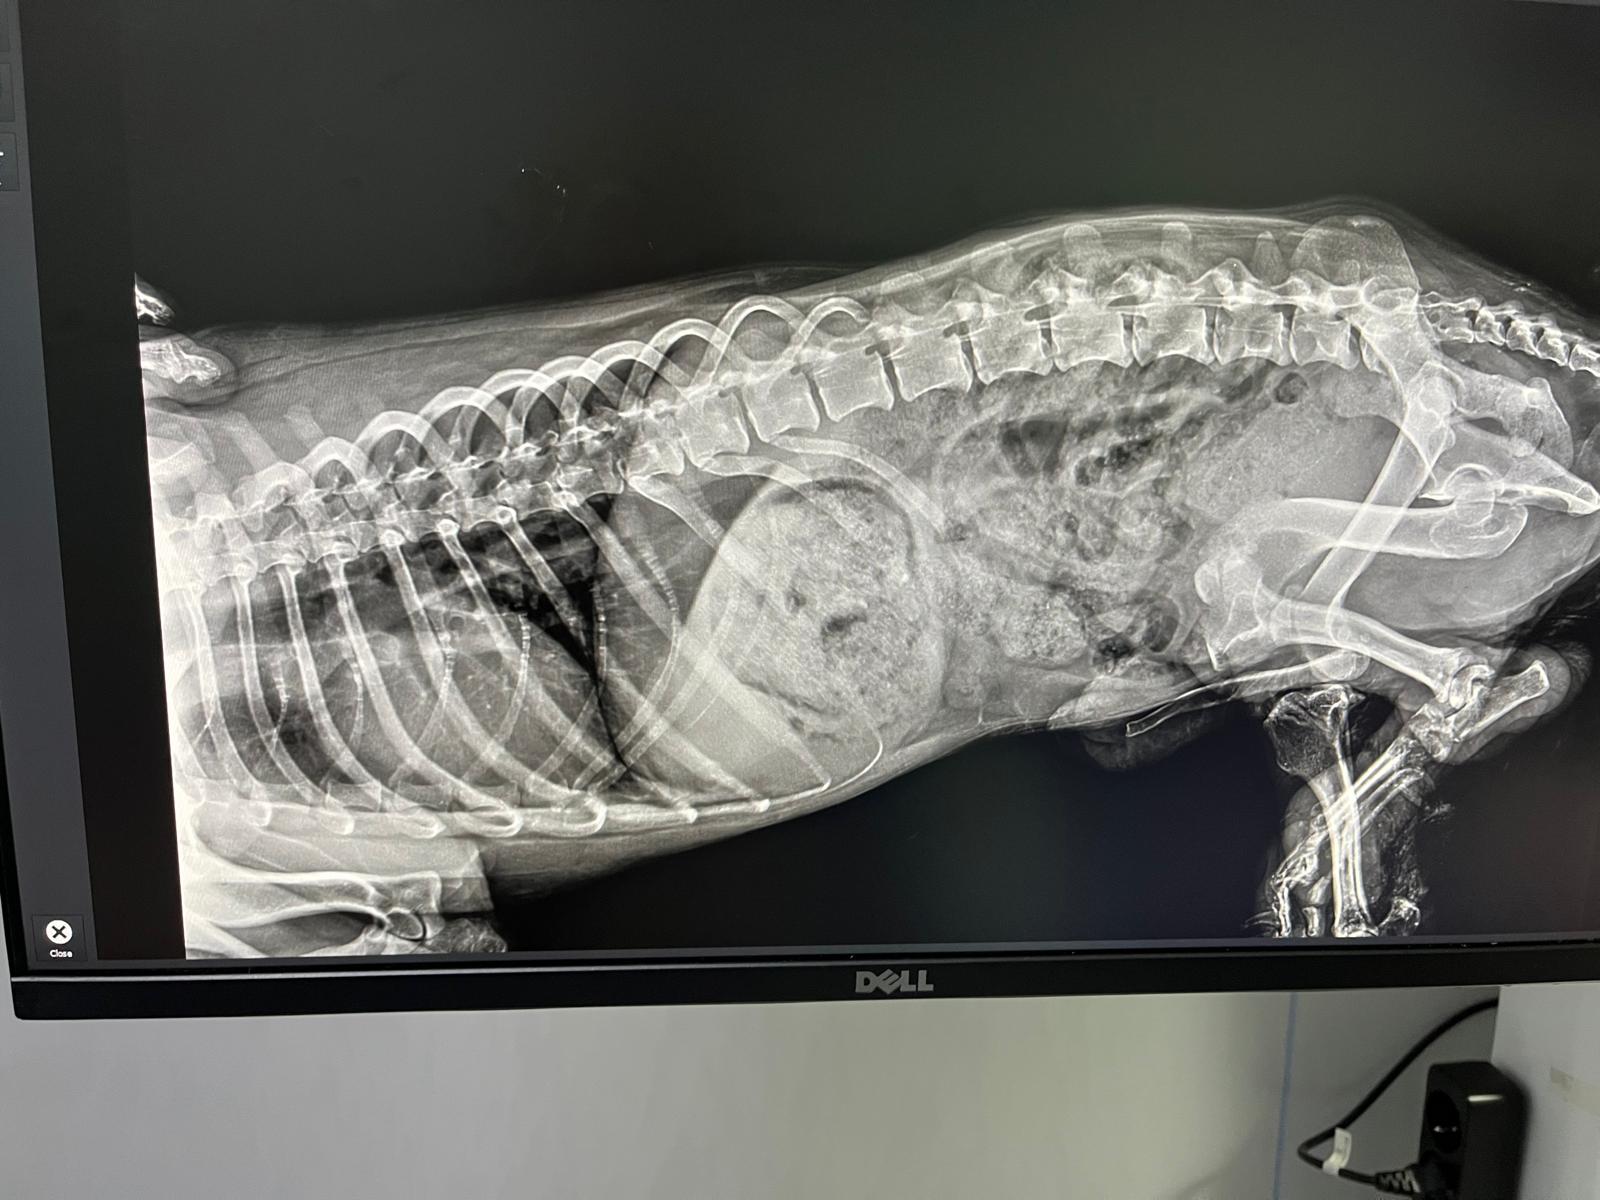

Jiro wurde jetzt geröngt. Laut Tierarzt ist seine Wirbelsäule intakt. Sein eines Bein hat ein Trümmerbruch. Das andere ist laut Tierarzt in Ordnung Dieses versucht er auch immer wieder aufzusetzen. Wir gehen davon aus, dass er zu lange gelegen hat und zu viel Muskulatur abgebaut hat. Aber für eine genauere Diagnose müsste er nach Deutschland reisen.

Röntgenbild vom Ende Oktober 2025